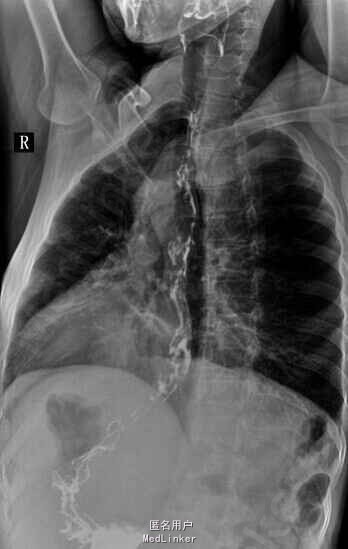

查体:慢性肝病体征,肝掌,蜘蛛痣阳性,腹水征阳性,压痛,反跳痛阴性。 辅查:肝功能示:谷丙260,谷草111.9,白蛋白34,总胆121,直胆80,ALP179,GGT200,凝血四项PT19,PTA41,甲胎蛋白86,HBV DNA7.9x10E4,肝炎系列未见异常,肝彩示肝硬化,食管钡餐示串珠样改变

诊断:乙肝肝硬化失代偿期、食管胃底静脉曲张 治疗:常规护肝退黄降酶治疗,制酸护胃,输血浆,白蛋白,利尿等对症支持治疗,予博路定抗病毒治疗。